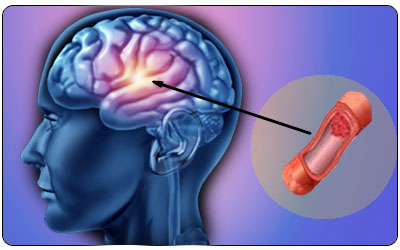

10.4172/lpma.1000115Risk Factors of Admission Delay after Ischemic Stroke in an Urban Tertiary Care Setting in China